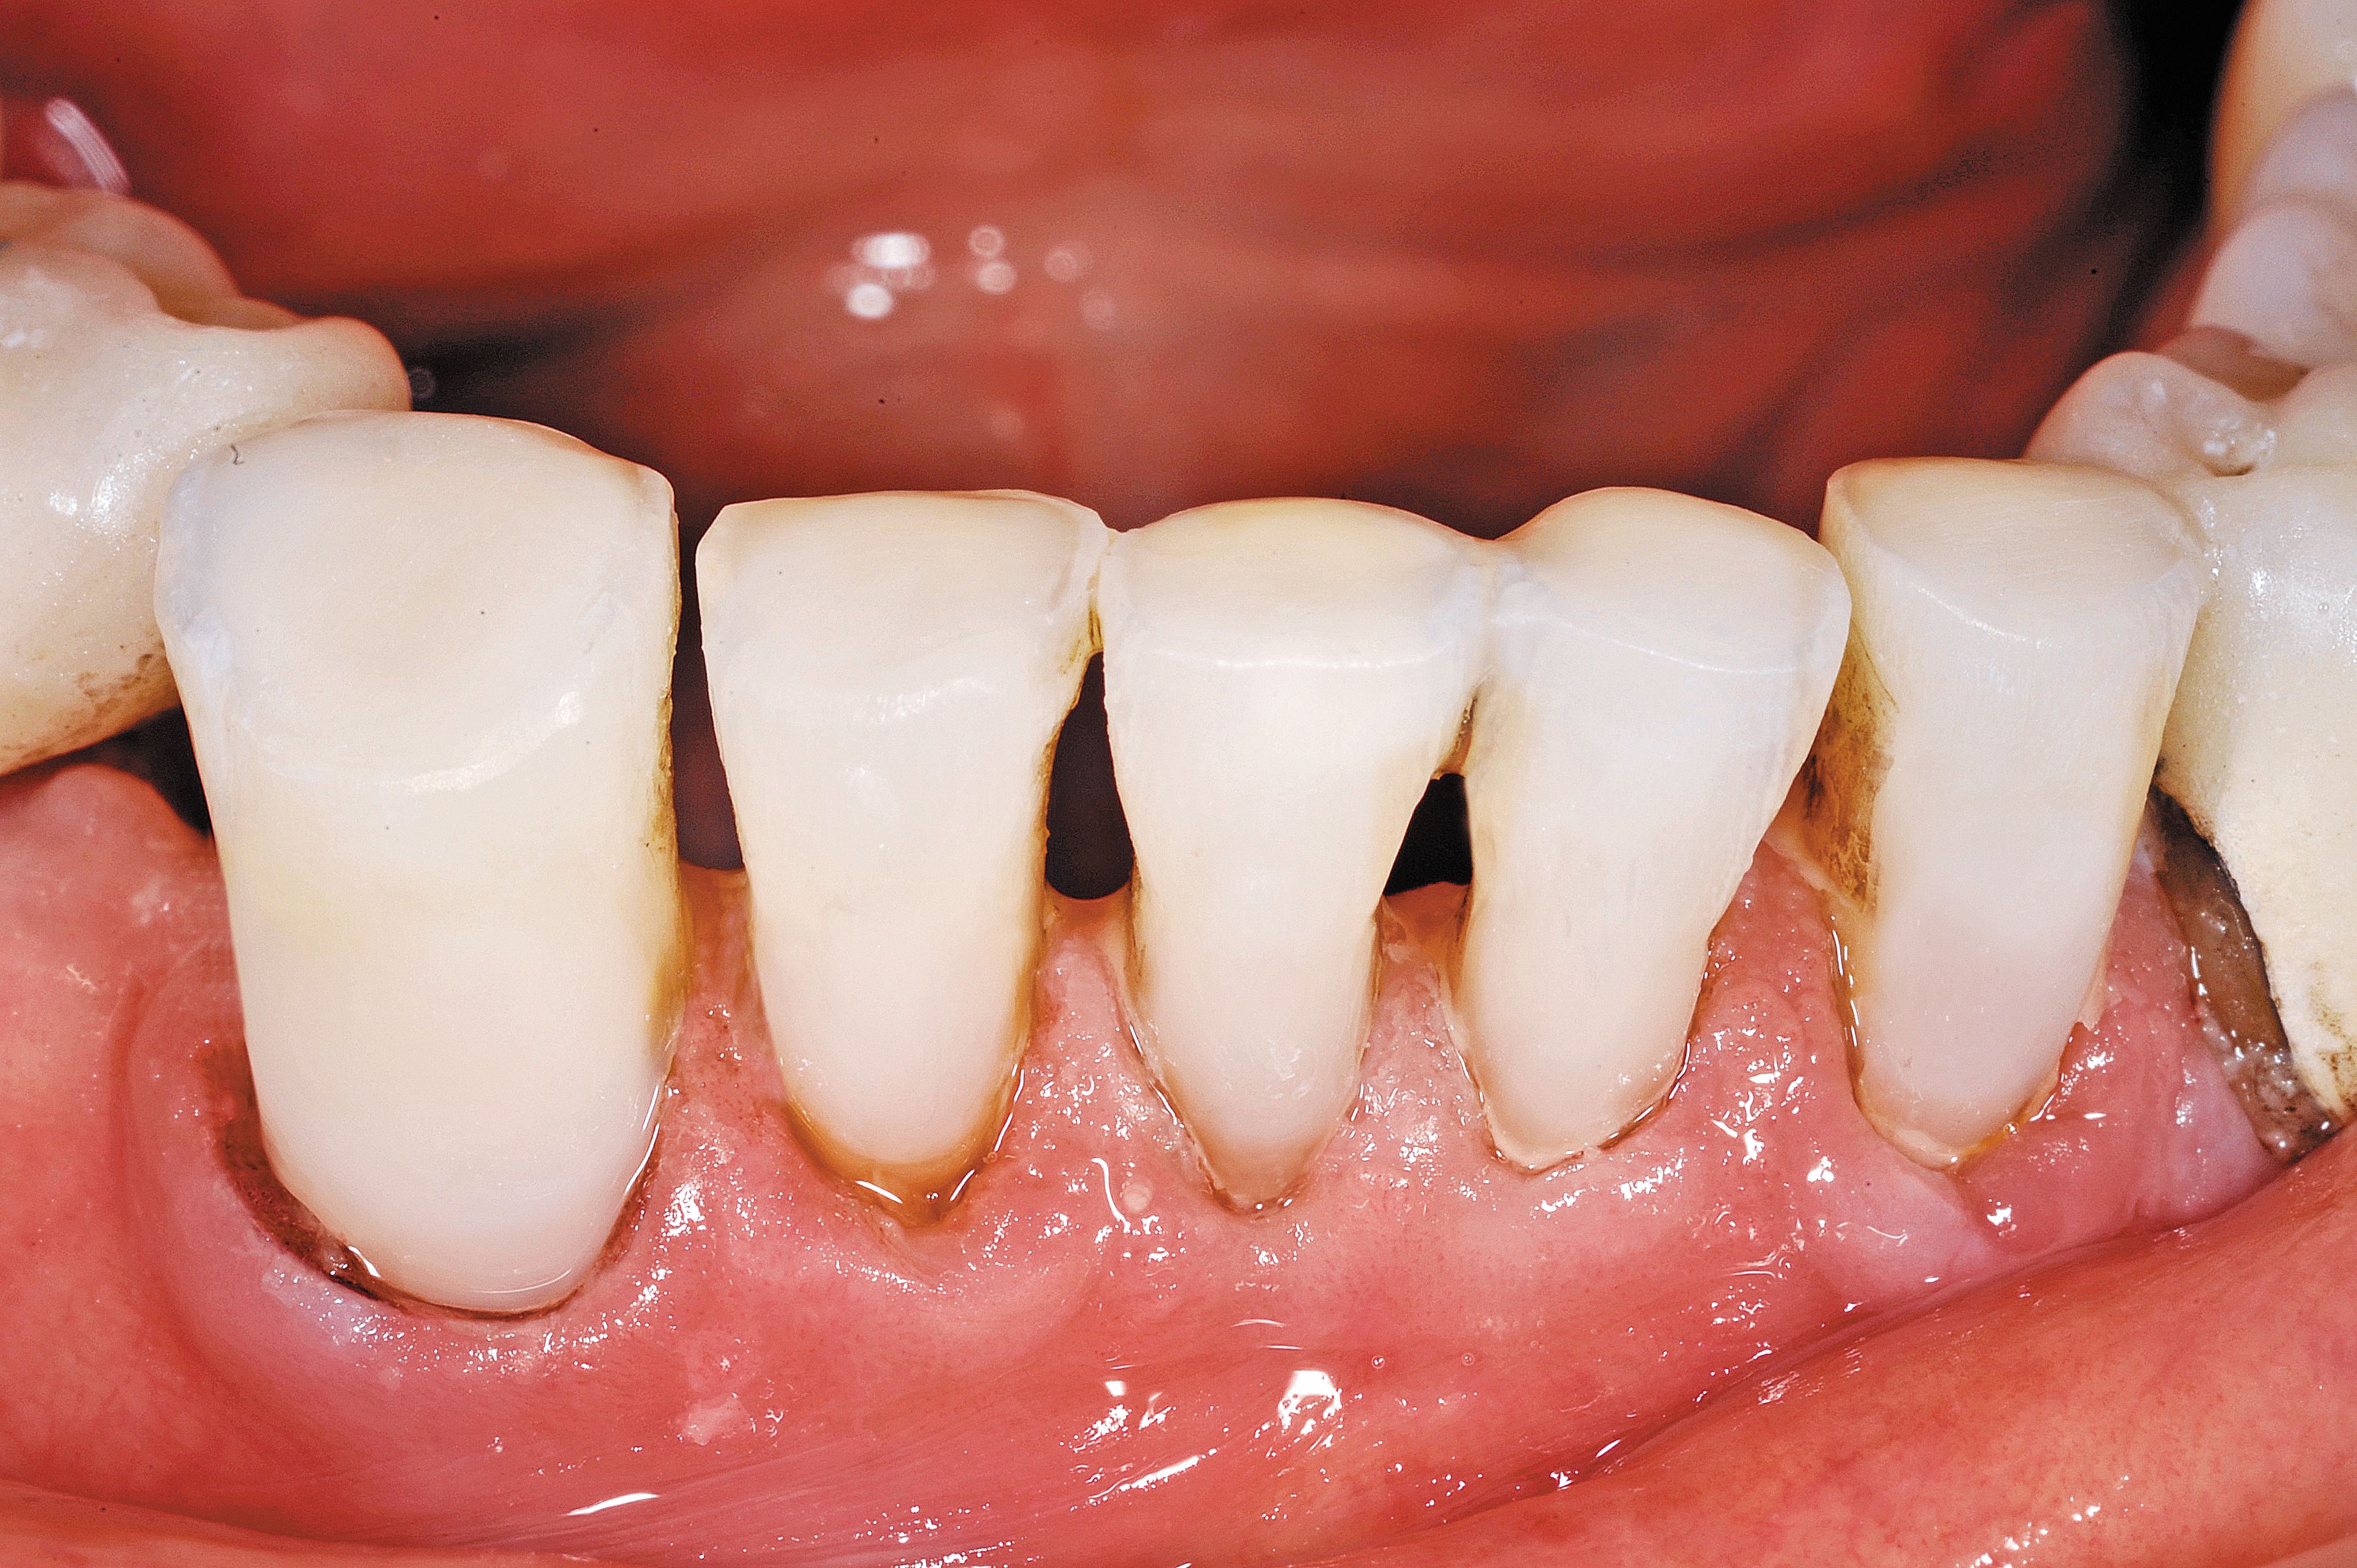

Fig. 1

In this case, the elderly gentleman had worn an upper denture for more than 50 years and was experiencing sensitivity to touch on the incisal edges of tooth Nos. 26 and 27. There was cold sensitivity on the lower incisor abfraction areas as well. There was also recurrent decay around the facial composite on the lower right bicuspid. He has been a chlorhexidine rinse user twice a day for more than 10 years, and staining was an ongoing issue (Fig. 1).